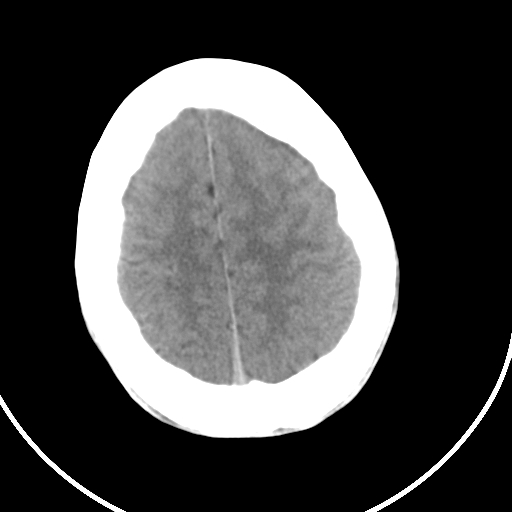

标题: CT21939:男20岁,外伤一年后,现头疼. [打印本页]

标题: CT21939:男20岁,外伤一年后,现头疼.

左侧额部硬膜外血肿机化、骨化。

左侧额部硬膜外血肿机化、骨化